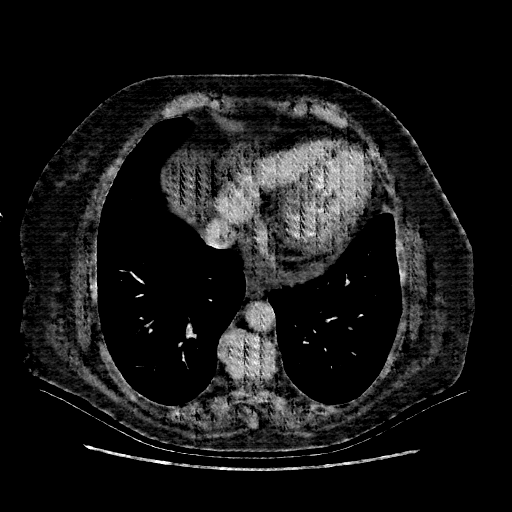

Generated VENOUS CT scan (A→B translation)

No window - Raw intensity values

Lung window (WL -600, WW 1500 β†’ Low βˆ’1350, High +150)

Mediastinum window (WL 40, WW 400 β†’ Low βˆ’160, High +240)